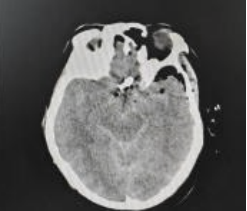

将近40岁的患者小刘(化名)因“突发意识不清2小时”急诊送到我院,患者来院时已陷入昏迷,且频繁恶心、呕吐,纪文军主任医师接诊后,考虑患者急性脑卒中可能,迅速指挥开通急诊卒中绿色通道,急诊完善头颅CT检查提示:蛛网膜下腔出血,考虑为颅内动脉瘤破裂所致。

术前CT提示蛛网膜下腔出血